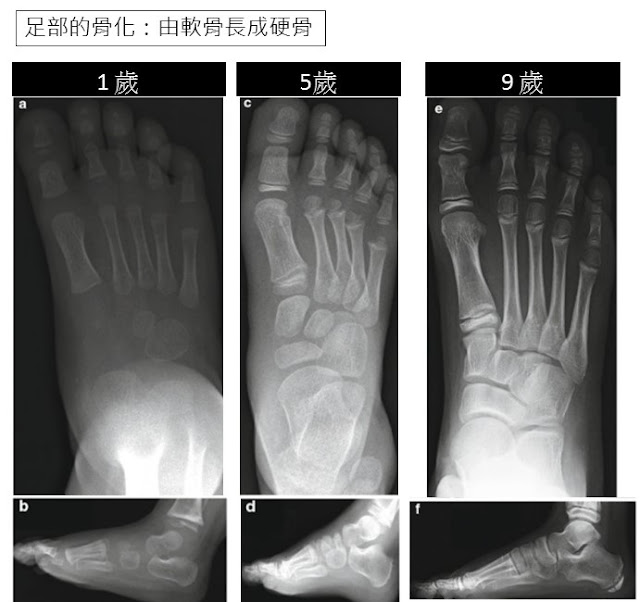

足部的骨化(ossification)

骨化作用從前足開始,從胚胎的過程中,骨化是從蹠骨(Metatarsal)的尾端開始→近→中→遠端趾骨;出生時所有蹠骨&趾骨已骨化完成。

(圖a&b)一歲小朋友足部的骨頭還是軟骨,尚未骨化完成,所以沒有足弓出現 (圖c,d)五歲幼童的跗骨已經開始骨化,但尚未完全發育完成,所以承重時足弓可能還是扁平的 (圖e,f)九歲的兒童足部發育已接近成熟。 |

跗骨(Tarsal bone)較晚開始骨化,妊娠24-28週,跟骨和距骨在出生後還繼續骨化,跟骨載距突在1-2歲後才會開始骨化、在5歲後才會完整發育;舟狀骨是最晚骨化的,通常在2-4歲。